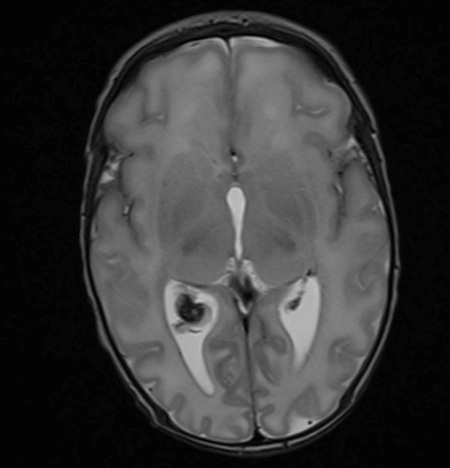

Con el objetivo de caracterizar mejor la lesión, se solicita RM, donde se evidencia un aumento de tamaño y engrosamiento del plexo coroideo derecho sugerente de plexitis como signo precoz de meningitis aguda, sin signos de ventriculitis.

Resonancia magnética. Aumento de tamaño y engrosamiento de plexo coroideo derecho sugerente de plexitis como signo precoz de meningitis aguda, sin signos de ventriculitis.